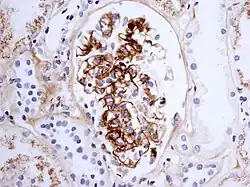

If there is doubt about the cause of the skin lesions, a biopsy of the skin may be performed to distinguish the purpura from other diseases that cause it, such as vasculitis due to cryoglobulinemia; on microscopy, the appearances are of a hypersensitivity vasculitis, and immunofluorescence demonstrates IgA and C3 (a protein of the complement system) in the blood vessel wall.[5] However, overall serum complement levels are normal.

Biopsy of the kidney may be performed both to establish the diagnosis or to assess the severity of already suspected kidney disease. The main findings on kidney biopsy are increased cells and Ig deposition in the mesangium (part of the glomerulus, where blood is filtered), white blood cells, and the development of crescents. The changes are indistinguishable from those observed in IgA nephropathy.[12]

The findings on renal biopsy correlate with the severity of symptoms: those with asymptomatic hematuria may only have focal mesangial proliferation while those with proteinuria may have marked cellular proliferation or even crescent formation. The number of crescentic glomeruli is an important prognostic factor in determining whether the patient will develop chronic renal disease.[8]